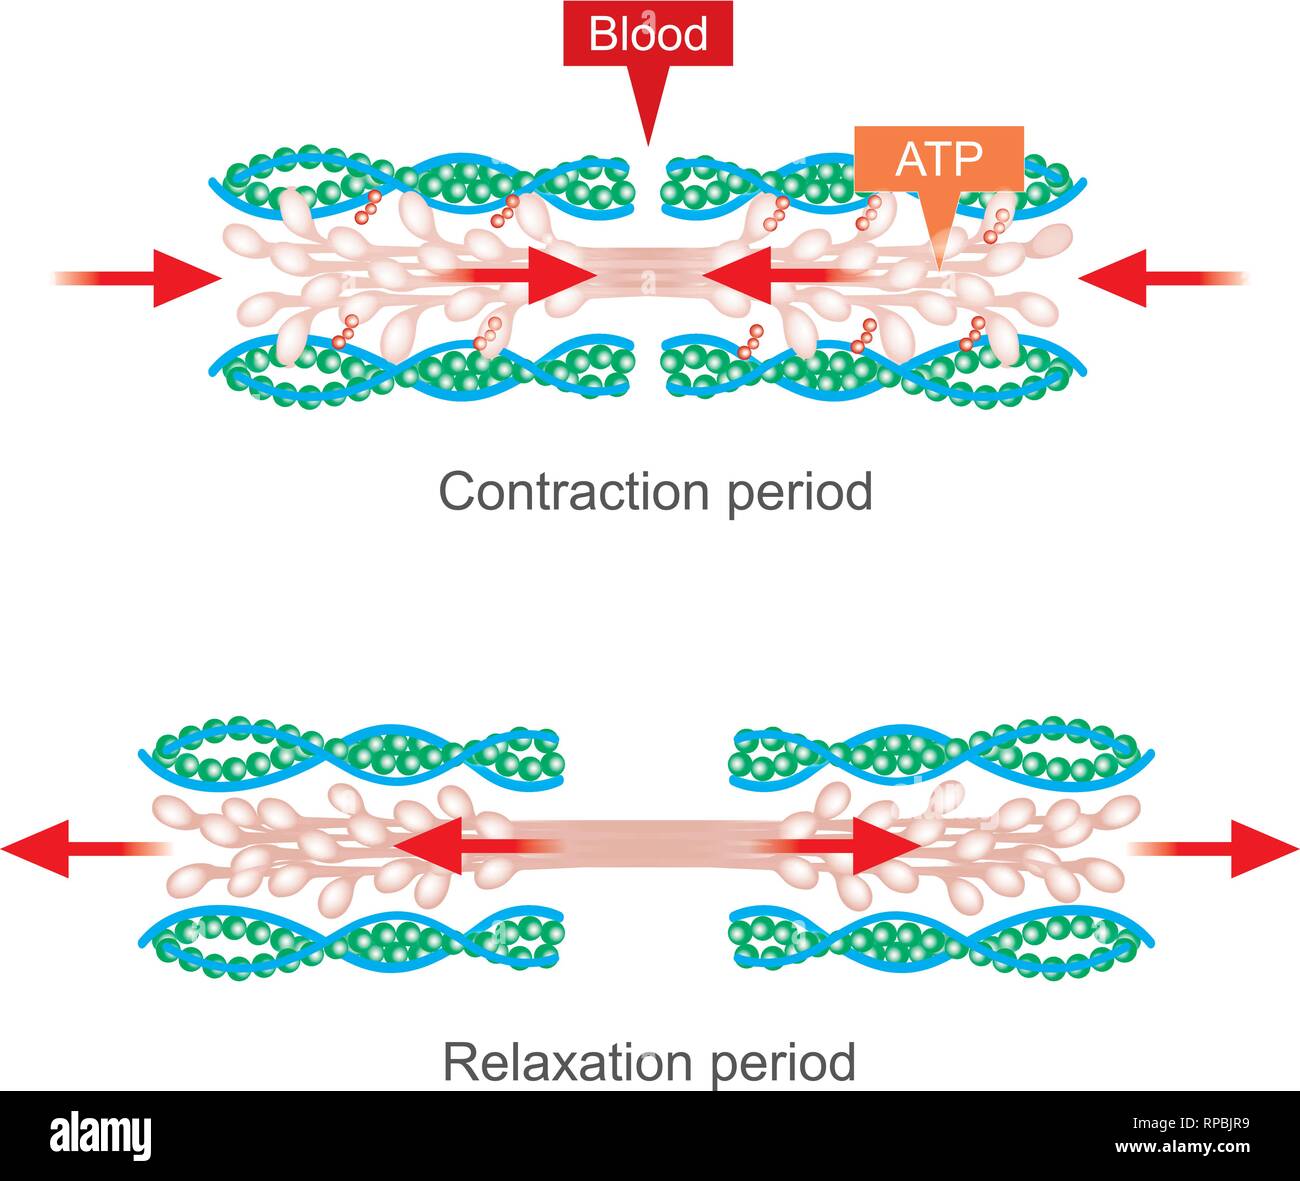

La contrazione muscolare come risultato di impulsi nervosi impostato su off una reazione biochimica che provoca nella miosina di stick di actina. Il corpo umano ed infografico. Illustrazione Vettorialehttps://www.alamy.it/image-license-details/?v=1https://www.alamy.it/la-contrazione-muscolare-come-risultato-di-impulsi-nervosi-impostato-su-off-una-reazione-biochimica-che-provoca-nella-miosina-di-stick-di-actina-il-corpo-umano-ed-infografico-image230481426.html

La contrazione muscolare come risultato di impulsi nervosi impostato su off una reazione biochimica che provoca nella miosina di stick di actina. Il corpo umano ed infografico. Illustrazione Vettorialehttps://www.alamy.it/image-license-details/?v=1https://www.alamy.it/la-contrazione-muscolare-come-risultato-di-impulsi-nervosi-impostato-su-off-una-reazione-biochimica-che-provoca-nella-miosina-di-stick-di-actina-il-corpo-umano-ed-infografico-image230481426.htmlRFRAY9BE–La contrazione muscolare come risultato di impulsi nervosi impostato su off una reazione biochimica che provoca nella miosina di stick di actina. Il corpo umano ed infografico.

La contrazione muscolare come risultato di impulsi nervosi impostato su off una reazione biochimica che provoca nella miosina di stick di actina. Il corpo umano ed infografico. Illustrazione Vettorialehttps://www.alamy.it/image-license-details/?v=1https://www.alamy.it/la-contrazione-muscolare-come-risultato-di-impulsi-nervosi-impostato-su-off-una-reazione-biochimica-che-provoca-nella-miosina-di-stick-di-actina-il-corpo-umano-ed-infografico-image237513453.html

La contrazione muscolare come risultato di impulsi nervosi impostato su off una reazione biochimica che provoca nella miosina di stick di actina. Il corpo umano ed infografico. Illustrazione Vettorialehttps://www.alamy.it/image-license-details/?v=1https://www.alamy.it/la-contrazione-muscolare-come-risultato-di-impulsi-nervosi-impostato-su-off-una-reazione-biochimica-che-provoca-nella-miosina-di-stick-di-actina-il-corpo-umano-ed-infografico-image237513453.htmlRFRPBJR9–La contrazione muscolare come risultato di impulsi nervosi impostato su off una reazione biochimica che provoca nella miosina di stick di actina. Il corpo umano ed infografico.